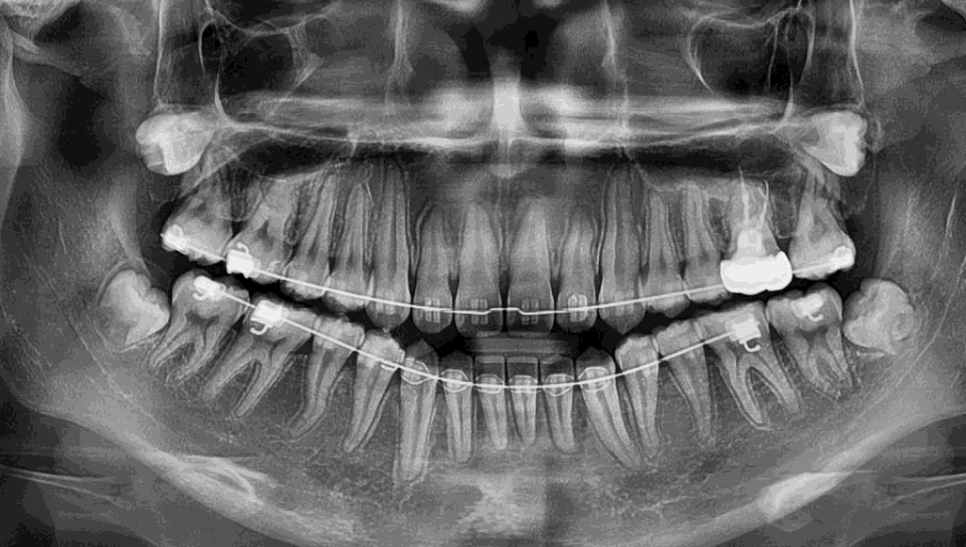

이번엔 10대 중반!

곧 고등학교에 진학을 하면

공부에 집중해야 되니

미리미리 구강문제를 해결하려고

부모님과 함께 방문을 해주셨어요.

집에서 가까운 곳에서 교정을 하고 있었는데

그 곳에서 사랑니 발치가 필요하다 하셨으며

역시나 강남레옹치과를 추천을 해주셔서 오시게 된 것!

위 경우보다 좀 더 나이가 어리다보니

확실히 뿌리도 더욱 적게 나있죠??

다 자라지 않았는데도

교정치료에 영향을 줄 수 있어서

뽑기로 결정했고,

멀리서 오신만큼 당일에 모두 진행해드렸어요.